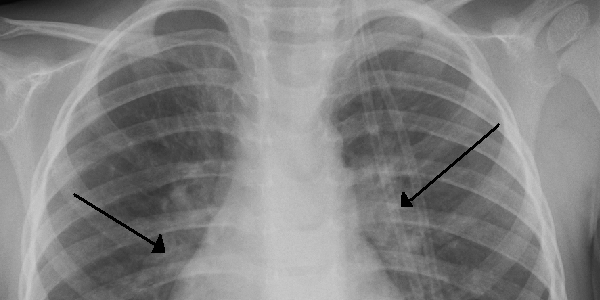

Qu’est-ce que la bronchiolite ? C’est une infection virale des petites bronches (les bronchioles) survenant principalement chez les nourrissons. Les causes sont souvent des virus contagieux qui débute généralement par un simple rhume et une toux pouvant être accompagnée de sifflements. La bronchiolite peut-être responsable de graves complications chez les enfants fragiles, notamment les enfants de moins de trois mois ou les bébés prématurés.